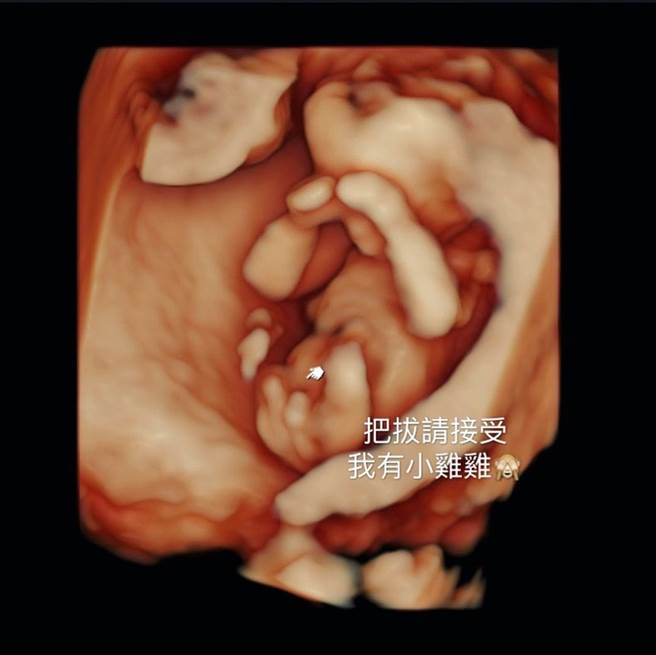

林可彤在脸书晒出超音波照片,开心宣布:「Adam弟弟来了」,并透露已经对丈夫说:「请接受我是妳今生唯一的女儿」,要他接受现实,第二胎都还没生出来,就先呼吁「拒绝劝生老三」,预告不会再生。

有趣的是,林可彤明知老公想要女儿,还特地在超音波照片中备注:「把拔请接受我有小鸡鸡。」更加打醒老公的女儿梦,并幽默直夸二宝「目前4个月鸡鸡这么大」,笑称:「从今以后育有二子的都是我妈妈团里的战友。」